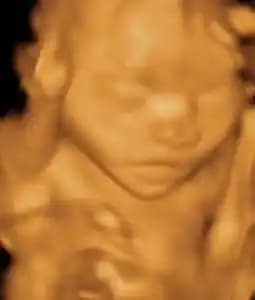

a baby human in the womb

"For you created my inmost being; you knit me together in my mother's womb."